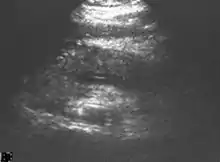

Ultrasound

On abdominal ultrasonography, the finding of a hypoechoic and bulky pancreas is regarded as diagnostic of acute pancreatitis.[24]